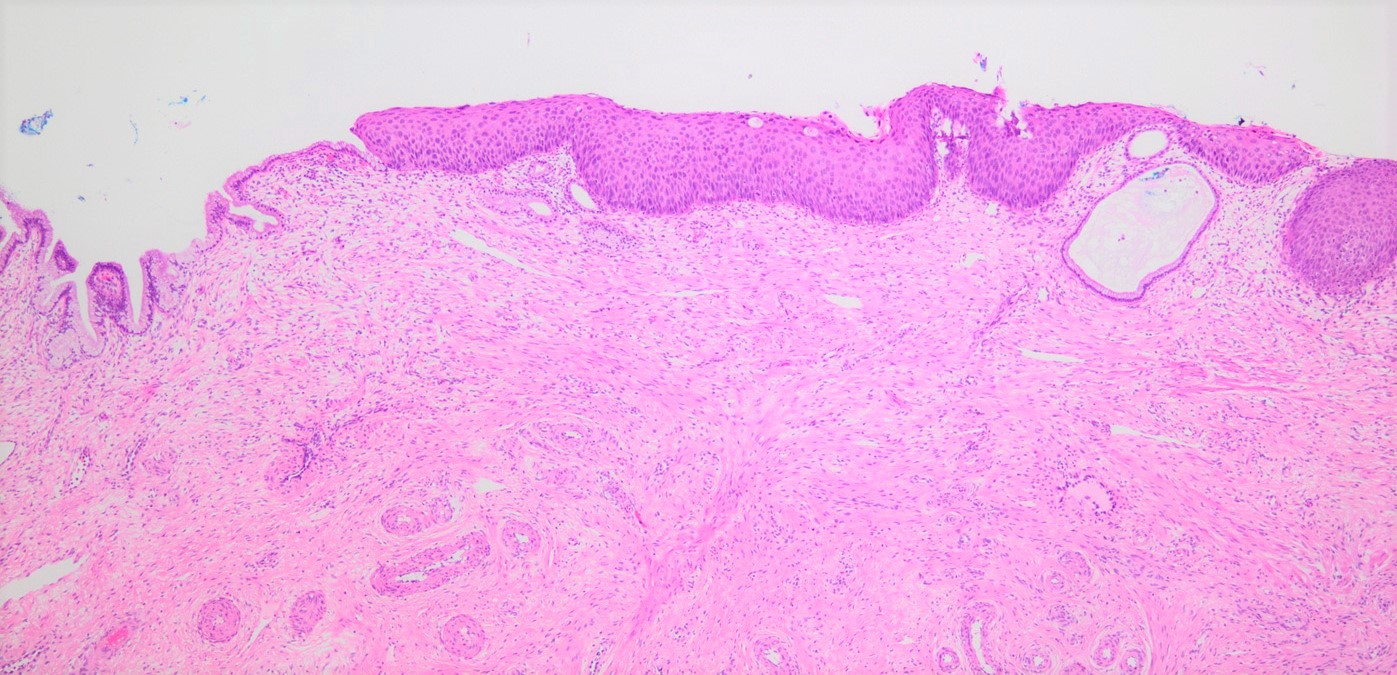

- Conventional / classic pattern: full thickness nuclear abnormalities (hyperchromasia, coarse chromatin, irregular nuclear contours and inconspicuous nucleoli), high N/C ratio in at least lower two - thirds of epithelium

- CIN II: cytoplasmic maturation in the upper third of mucosa

- CIN III: full thickness basal / parabasal type, no maturation difference across layers

- Increased mitotic activity with atypical mitoses

Microscopic (histologic) images

Contributed by Khaled J. Alkhateeb, M.B.B.S.